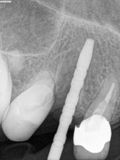

fredlibc | all galleries >> Galleries >> NSankhyan - immediate 13, impls 1121 and 25 with grafting > 13.jpg